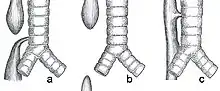

| Common anatomical types of esophageal atresia a) Esophageal atresia with distal tracheoesophageal fistula (86%), Gross C. b) Isolated esophageal atresia without tracheoesophageal fistula (7%), Gross A. c) H-type tracheoesophageal fistula (4%), Gross E.[1] | |

This condition takes several different forms, often involving one or more fistulas connecting the trachea to the esophagus (tracheoesophageal fistula).

| Type A | Type 2 | I | "Long Gap", "Pure" or "Isolated" Esophageal Atresia | Characterized by the presence of a "gap" between the two esophageal blind pouches with no fistula present. | 7% |

| Type B | Type 3A | II | Esophageal Atresia with proximal TEF (tracheoesophageal fistula) | The upper esophageal pouch connects abnormally to the trachea. The lower esophageal pouch ends blindly. | 2-3% |

| Type C | Type 3B | III, IV | Esophageal Atresia with distal TEF (tracheoesophageal fistula) | The lower esophageal pouch connects abnormally to the trachea. The upper esophageal pouch ends blindly. | 86% |

| Type D | Type 3C | V | Esophageal Atresia with both proximal and distal TEFs (two tracheoesophageal fistulas) | Both the upper and lower esophageal pouch make an abnormal connection with the trachea in two separate, isolated places. | <1% |

| Type E | Type 4 | - | TEF (tracheoesophageal fistula) ONLY with no Esophageal Atresia, H-Type | Esophagus fully intact and capable of its normal functions, however, there is an abnormal connection between the esophagus and the trachea. Not included in classification by Ladd | 4% |